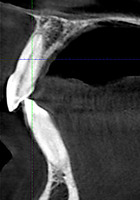

При анализе и описании компьютерной конусно-лучевой томографии (рис. 2а-г) была выявлена генерализованная первичная дегисценция вестибулярной пластинки кости от 1/2 до 3/4 длины корней зубов, зубной ряд целостный, все зубы витальны, кариозных поражений нет. Тип кости 1-2 (Lechkolm и Zarb, 1983), первичная дегисценция вестибулярной костной пластинки превышает пределы возрастной атрофии.

Через 12 месяцев (рис. 7а-г) на срезах компьютерной томограммы 11-ый и 13-ый зубы находятся в костной ткани, при этом костные пики и перегородки укрепились, объем их увеличился; вестибулярно заметен объем костной массы, предположительно компактной формации, исходя из электронной плотности участка. Этим объясняется отсутствие рецидива при лечении рецессии десны как в случае применения аутотрансплантата, также и ТМО (dura mater).